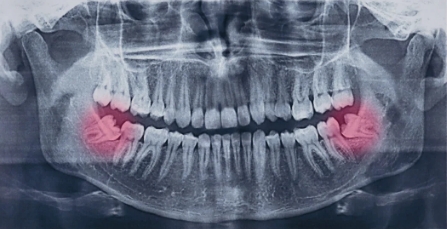

Fjerning av visdomstenner når man er ung er lettere, man gror bedre og det blir mindre komplikasjoner når man er ung. Det er vanskelig å sette et absolutt skille når det gjelder alder, men generelt anbefales det at visdomstenner fjernes før man er 30 år. En forutsetning er selvsagt at det er en grunn (en indikasjon) for at de skal fjernes. Alder er i seg selv ikke en indikasjon, men påvirker likevel hvor tydelig grunnlag man må ha for å anbefale fjerning. I forhold til alder er det spesielt visdomstenner i underkjeven som er viktige å vurdere – dette har med benstruktur, kjevevinkel og nærhet til nærliggende nerver å gjøre.